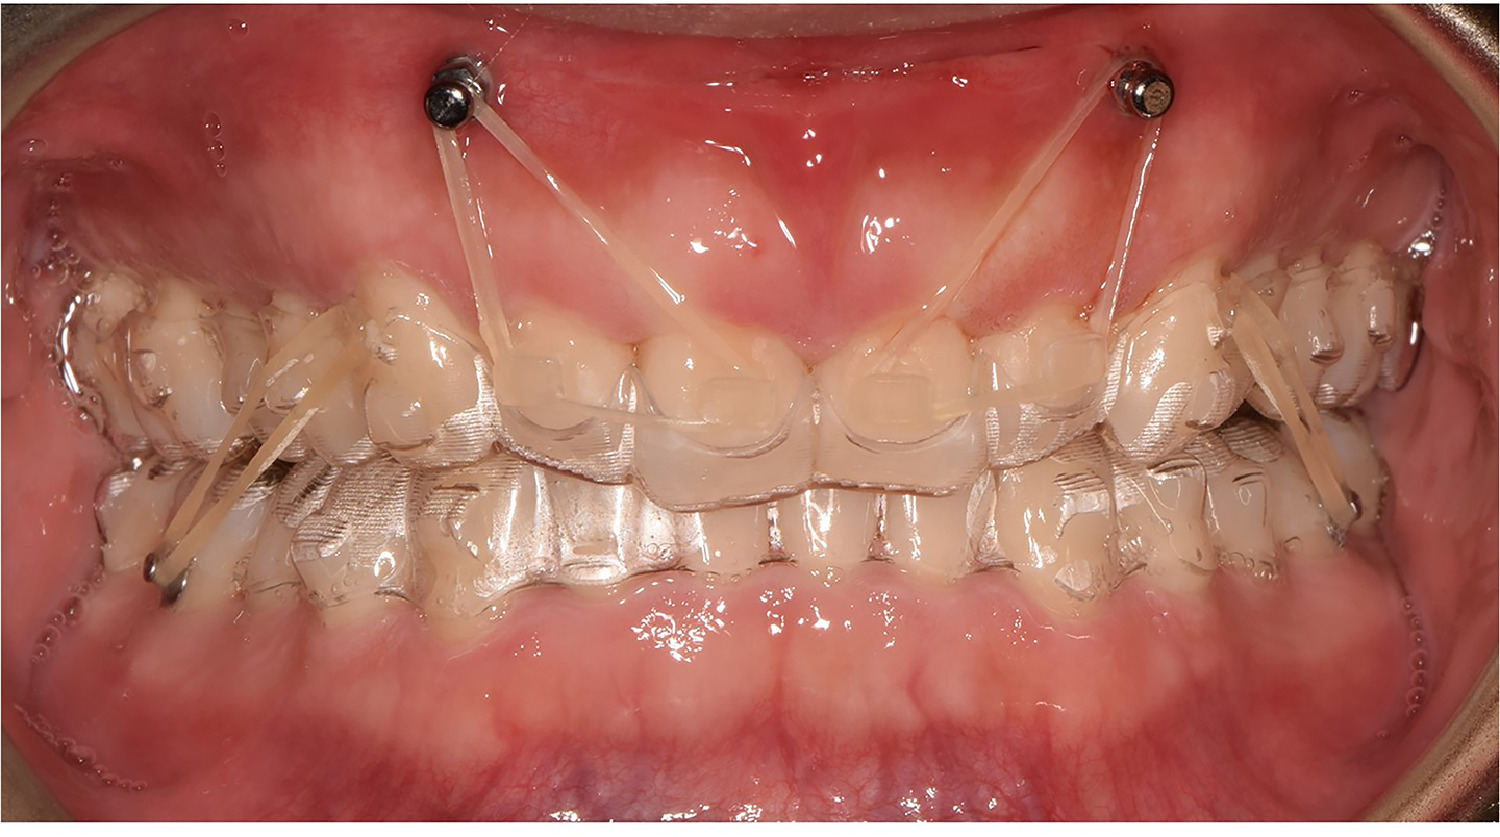

Mini-vis TAD avec aligneurs transparents pour cas complexes

Cas complexes adultes

Pour les adultes ne pouvant ou ne souhaitant pas subir une chirurgie orthognathique, les mini-vis offrent une alternative viable avec d'excellents résultats.